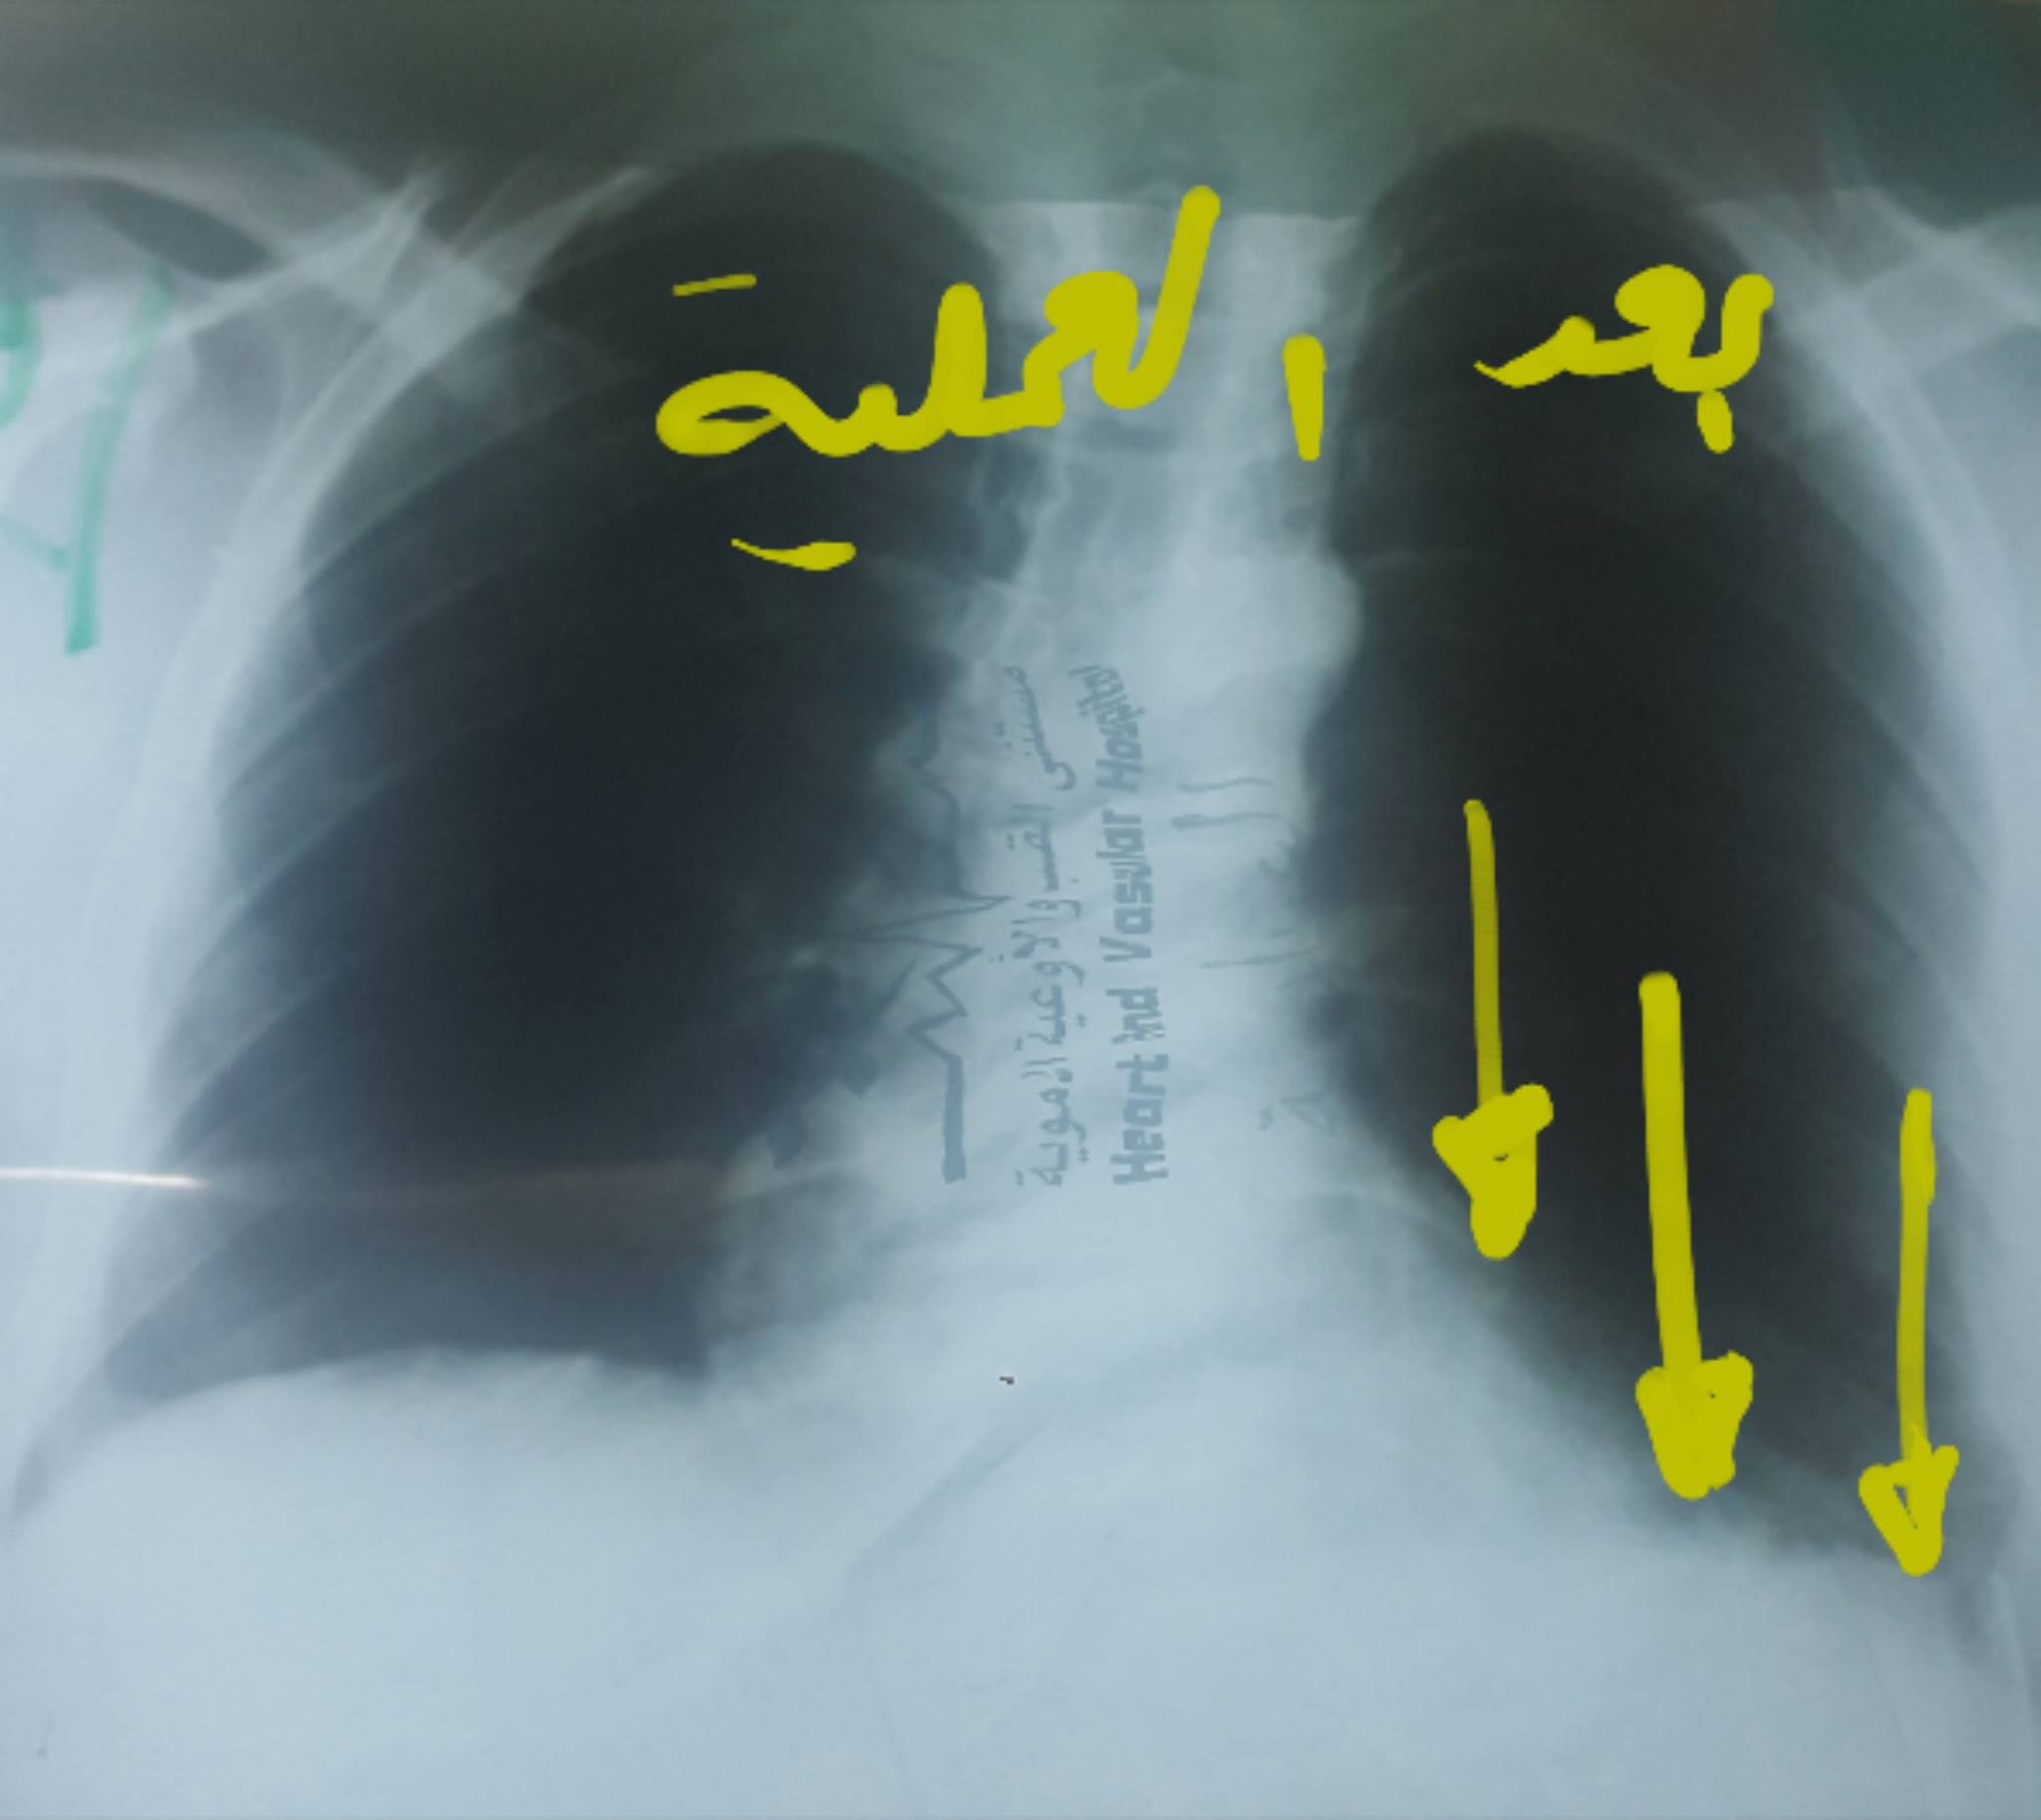

بالصور: إجراء عملية جراحية نوعية بمستشفى الخدمة العامة

غزة - فلسطين الآن

من جديد نجح الفريق الطبي بمستشفى الخدمة العامة برئاسة د. رائد العريني استشاري مناظير وجراحة الصدر والتشوهات الخلقية الصدرية والروبوت الجراحي وزراعة الرئة. و مساعده د.طارق شراب أخصائي الجراحة العامة وفريق العمليات بالمستشفى من إجراء عملية نوعية جديدة للمريض ز .ح البالغ من العمر 25 عام والذي يعاني من ضيق في التنفس منذ سنوات .

وأوضح د رائد العريني أن المريض يعاني منذ سنوات من ضيف في التنفس وحضر إلى المستشفى وقد أجري له الفحص الطبي الإكلينيكي والصور الإشعاعية والمقطعية حيث تبين وجود ارتخاء شديد لعضلة الحجاب الحاجز الأيسر مما يتسبب بصعود الحجاب الحاجز وأحشاء البطن من معدة وقولون والطحال إلى تجويف الصدر مانعا لتمدد الرئة اليسرى وصعوبة في التنفس.

والجدير ذكره أن د. العريني أجرى خلال الشهر الجاري عملية لمريض آخر يعاني من نفس المشكلة حيث لاقت نجاحا باهرا بحيث تحسنت حالة المريض بشكل كبير بعد إجراء العملية.

وأكد العريني أن المريض غادر المستشفى بصحة جيدة بعد مكوثه 3 أيام نقاهة، شاكرا الجهود المبذولة.